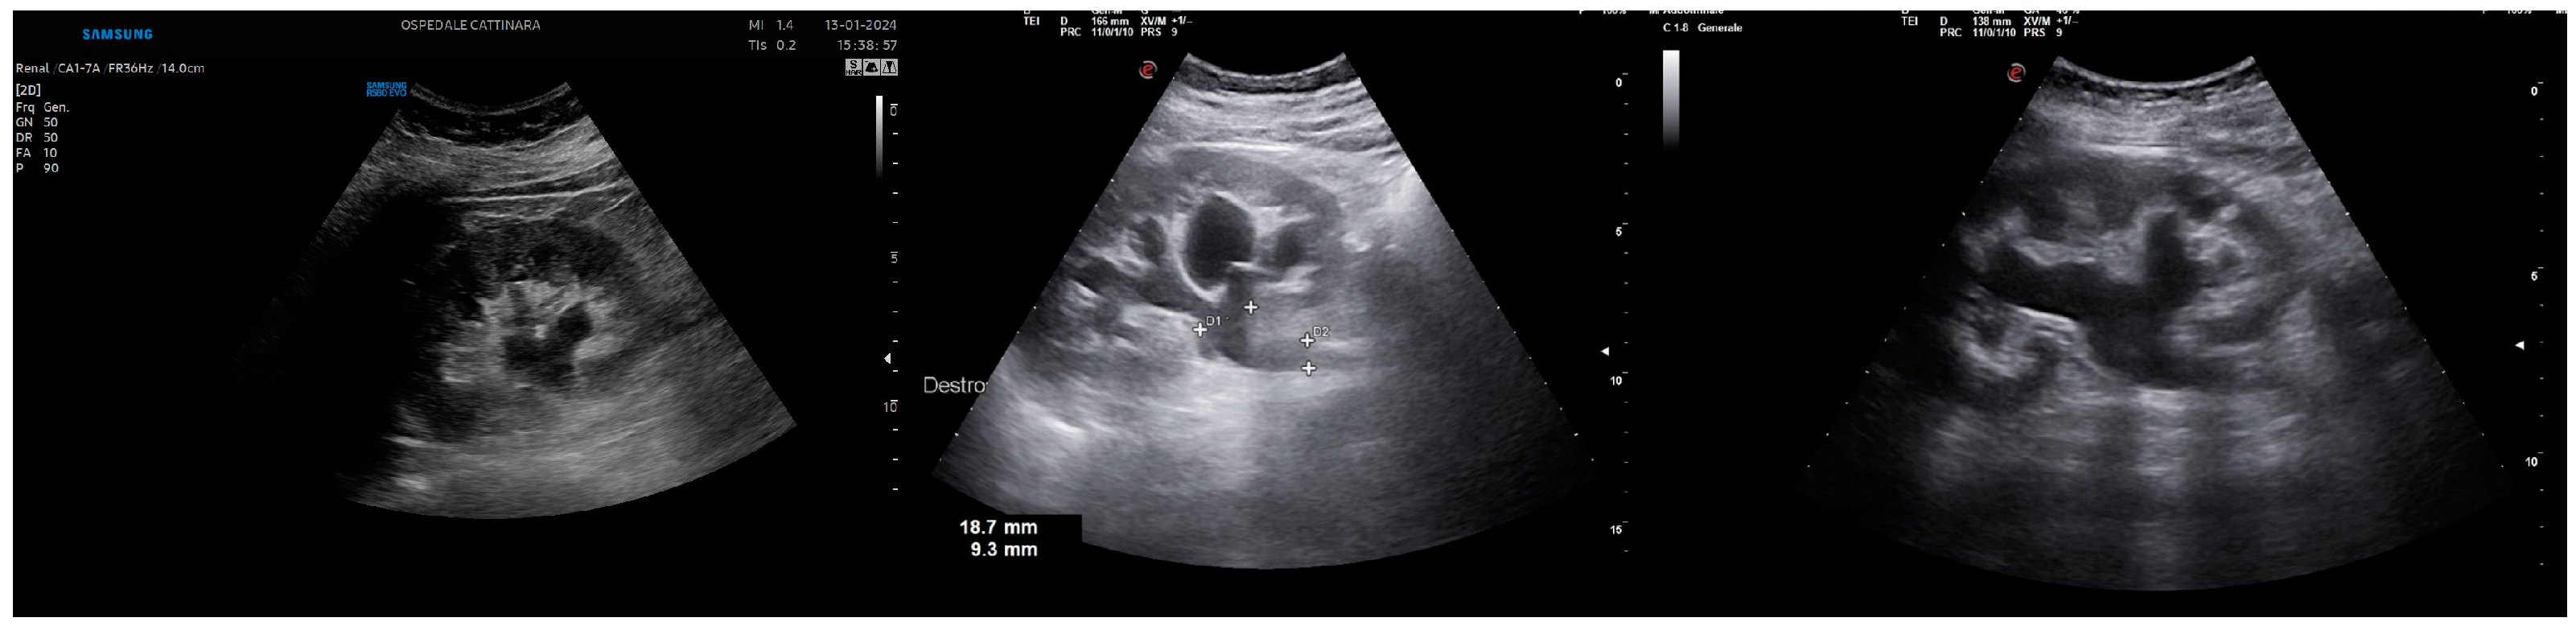

3.4. Ureteral Stone

3.5. The “Twinkling” Artifact